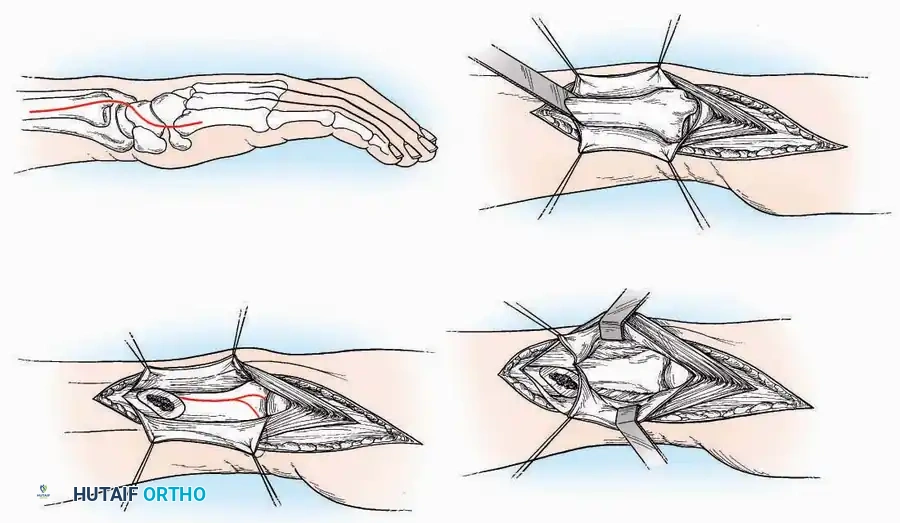

Approaches to the Interphalangeal (IP) Joints

Indications: Arthrodesis for hammer toe deformities, excision of intra-articular osteophytes, or reduction of irreducible dislocations.

Surgical Technique:

* Great Toe: Make a 2.5 cm longitudinal incision strictly on the medial midaxial aspect of the toe.

* Fifth Toe: Utilize a lateral midaxial incision to avoid interdigital maceration.

* Lesser Toes (2nd, 3rd, 4th): Approach the IP joints through a dorsal longitudinal incision placed just lateral to the corresponding extensor digitorum longus (EDL) tendon.

* Deep Dissection: Carry the dissection sharply through the subcutaneous tissue and superficial fascia directly to the joint capsule.

* Neurovascular Protection: Reflect the skin edges with meticulous care. Retract the dorsal digital nerves and vessels dorsally, and the plantar nerves and vessels plantarward.

* Capsulotomy: Open the capsule either transversely (for joint resection/arthrodesis) or longitudinally (for exploration), exposing the articular surfaces.